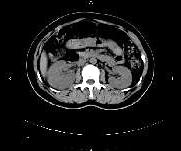

问题 女,27岁,寒战高热、尿频、尿痛3天,尿检:白细胞(+++),CT平扫及增强扫描如图所示,下列说法错误的是 ( )

选项 A、考虑为急性肾盂肾炎 B、考虑为慢性肾盂肾炎 C、增强后可见条片状密度减低区 D、左肾未见异常 E、右肾体积增大

答案 B